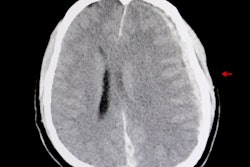

A blood test that detects biomarkers for brain injury could help rule out patients suspected of having traumatic intracranial injuries, thus avoiding the need for CT scans, according to a large multicenter observational trial published online July 24 by Lancet Neurology.

Researchers from the U.S and Europe found the blood test correctly identified 99.6% of patients who did not have a traumatic intracranial injury on head CT scans in a study of more than 1,900 adults -- mostly with mild traumatic brain injury (TBI) -- who presented to emergency departments in the U.S. and Europe.

Routine use of the new biomarker test in emergency departments could reduce head CT scans by a third in patients with acute head injury thought to be in need of CT scanning, avoiding unnecessary CT-associated costs and radiation exposure, with a very low false-negative rate, according to Dr. Jeffrey Bazarian at the University of Rochester School of Medicine in Rochester, NY, who co-led the research.

But sending too many ER patients on for CT scans if they turn out to be negative for brain injury could expose some individuals to unnecessary radiation, while also using up hospital resources. Could these patients be triaged in another way?